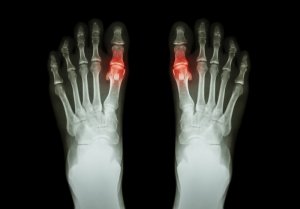

Gikt er en sykdom som forårsakes av at mikrokrystaller av urinsyre opphoper seg i leddene. Disse krystallene buler ut under huden eller de avleirer seg i urinrøret.

Den konstante nedbrytingen og oppbyggingen av celler, slik som inntak av visse mattyper, produserer et nivå av urinsyre i blodet. Kroppen renser og tar bort dette normalt sett ved hjelp av nyrene. Men når det ikke er nok, vil nivåene av urinsyre øke unaturlig. Krystaller dannes og lagres i leddene, noe som utløser sterke smerter.

- Vanligvis er leddene som er angrepet varme og røde (betente). Oftest er de også veldig følsomme og hovne.